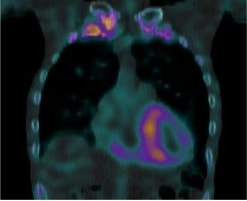

サルコイドーシスは、非乾酪性肉芽腫という病理変化を伴う炎症性疾患です。心臓以外にも眼、皮膚、肺やリンパ節に起こり得ます。心臓においては、心筋の収縮障害から進行すれば心拡大が起きます。不整脈を併発しやすいことも知られています。診断には心臓MRIや血液検査のほかに、心臓にブドウ糖が取り込まれているか調べる核医学検査であるFluorodeoxyglucose-Positron Emission Tomography(FDG-PET)が病勢の把握に有用です。

心サルコイドーシスの活動期

ステロイド治療により

炎症・免疫反応が軽減